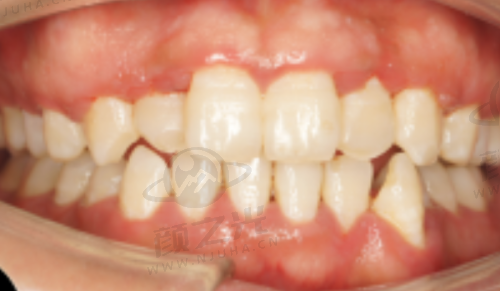

隐形矫正:提供隐形矫正服务,采用透明的矫正器,美观舒适且不易察觉。对于那些追求美观,不想因佩戴传统矫正器而影响形象的患者来说,是非常合适的选择。